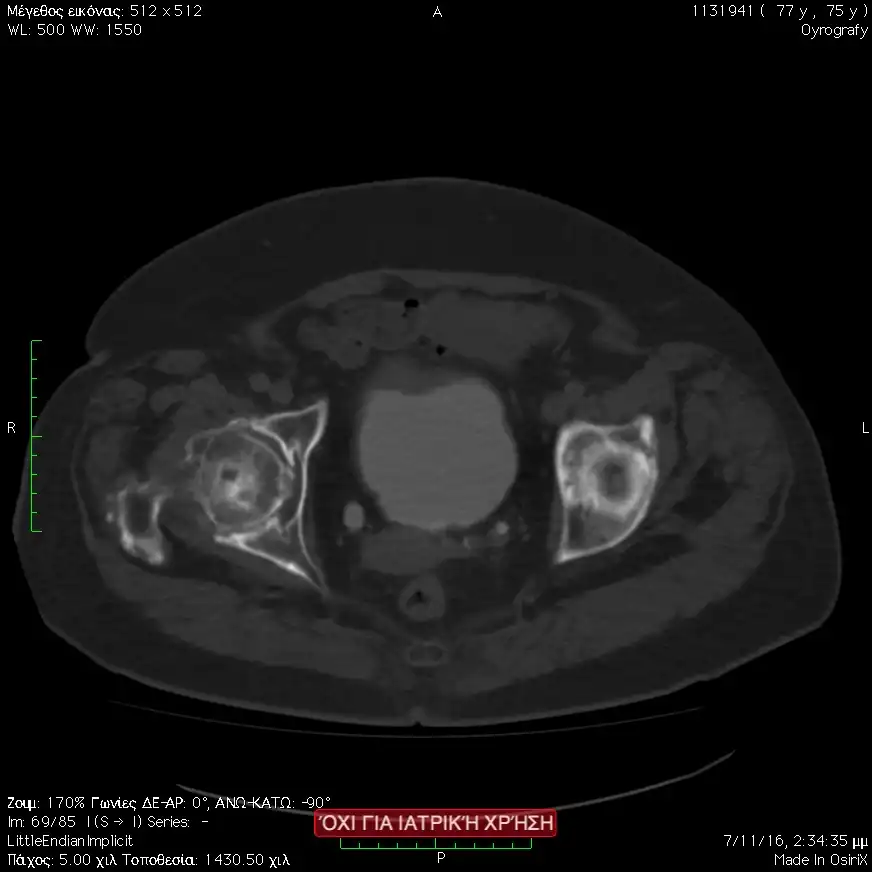

Η αξονική ουρογραφία ή εναλλακτικά η ενδοφλέβιος πυελογραφία χρησιμοποιούνται για την ανίχνευση μορφωμάτων στην ουροφόρο οδό με την ανάδειξη ελλειμμάτων πλήρωσης.